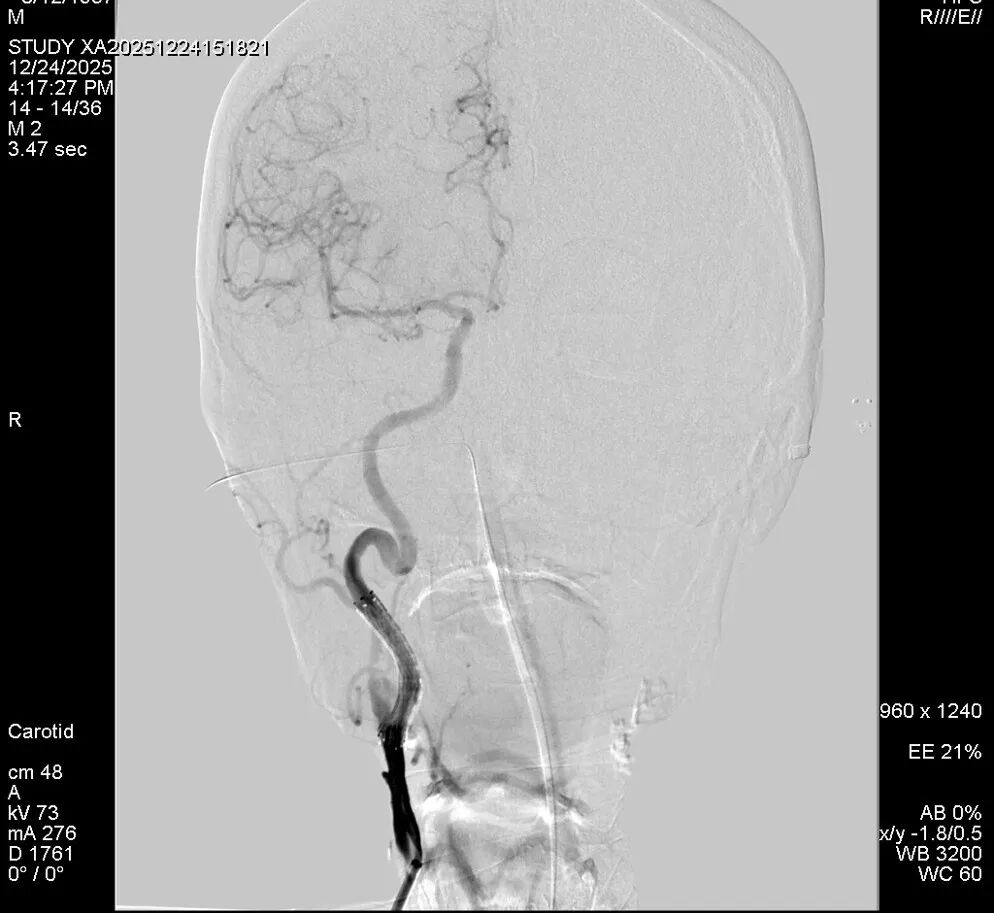

面对如此棘手的局面,颅底外科中心组织了全院病例讨论,耳鼻咽喉头颈外科、颅底外科、神经外科、血管外科、影像科、肿瘤科等各专业术20多位主任医师进行了紧急讨论。佟小光院长带领的血管外科团队果断决策,患者颈内动脉长程受到破坏接受开颅高流量搭桥手术应是最优选择,但是患者身体状态差而且经前期抢救后心理状态差惧怕搭桥手术,可以选择局麻微创血管内介入治疗,这样能为患者赢得宝贵的时间获得二期病变切除和颅底修复的机会。经过充分准备,环湖医院王红光副院长和复合脑血管外科尚彦国主任联手为患者在局麻状态进行了左侧颈内动脉破裂处第二枚覆膜支架的植入,将破裂点彻底封堵,同时在右侧重度狭窄的颈内动脉植入了扩张支架,这样既避免了再次出血的风险也保证了患者颅内的供血,为后续根治手术创造了至关重要的前提条件。

我院CTA检查:左侧颈内动脉覆膜支架术后,假性动脉瘤消失

术后DSA:右侧颈内动脉支架后通畅,左侧颈内动脉岩骨段覆膜支架后假性动脉瘤消失